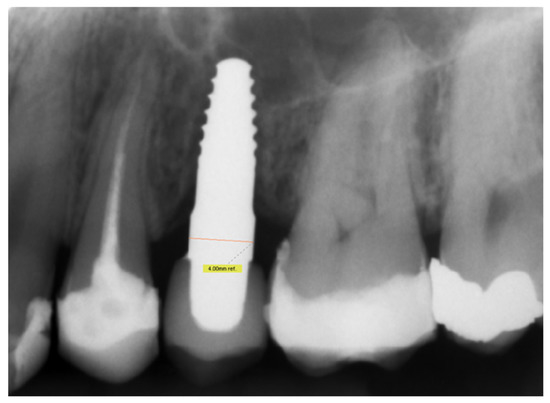

2.4. Radiographic Evaluation

3.3. Radiographic Assessments

| MBL | baseline | 16 | 0.69 | 2.19 | 1.40 | 0.43 | |

| 4 years | 14 | 1.12 | 3.07 | 1.99 | 0.57 | p = 0.001 | |

| 8 years | 12 | 0.83 | 2.85 | 1.70 | 0.64 | p = 0.019 | |

| 11 years | 11 | 1.01 | 2.60 | 1.59 | 0.53 | p = 0.027 | |

| resorption | 14 | −0.55 | 1.27 | 0.43 | 0.48 | p = 0.005 |